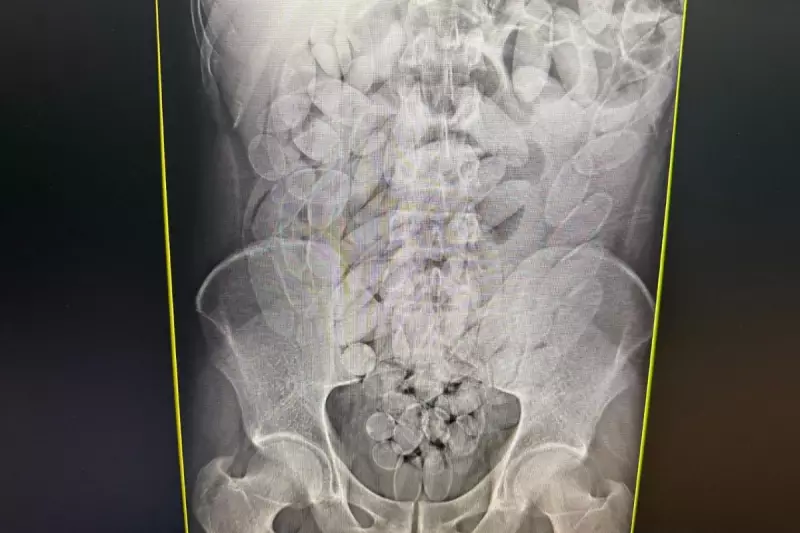

Uma operação da Polícia Federal em Corumbá, Mato Grosso do Sul, resultou na prisão de oito cidadãos bolivianos que transportavam cocaína de forma extremamente arriscada. Os suspeitos haviam ingerido 645 cápsulas contendo a droga, totalizando aproximadamente 7 quilos de cocaína pronta para distribuição no mercado ilegal.

O método de ingestão das cápsulas representa um perigo mortal para os transportadores, conhecidos como "mulas" do tráfico. Qualquer rompimento das embalagens no estômago ou intestino pode causar overdose imediata e levar à morte.

• 645 cápsulas de cocaína apreendidas

• 8 suspeitos bolivianos detidos

• Aproximadamente 7 quilos de droga

Os presos passarão por avaliação médica para garantir que todas as cápsulas sejam eliminadas de seus organismos de forma segura, sob supervisão de profissionais de saúde.